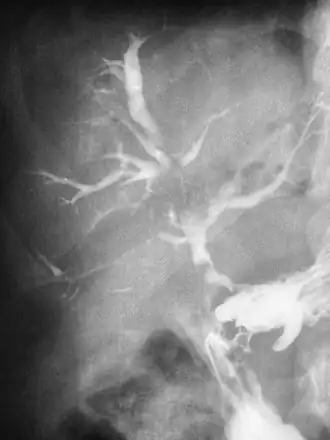

Een fistel (Latijn: fistula) of pijpzweer is een niet-natuurlijk kanaal (aangeboren, kunstmatig aangebracht of door verzwering ontstaan) tussen twee lichaamsholten of tussen een lichaamsholte en de huid. Een fistel kan ook een opening zijn tussen een klier en de huid.

Een fistel ontstaat meestal na een ontsteking in de lichaamsholte of in de klier. Als de ontsteking zich heeft uitgebreid tot de huid kan deze spontaan openbreken, of worden doorgebroken. Als de ontsteking zelf is genezen, kan er toch een fistel overblijven, waar af en toe weer vuil of vocht uit naar buiten kan komen. Vaak groeit de fistel echter vanzelf weer dicht als de ontsteking is genezen.